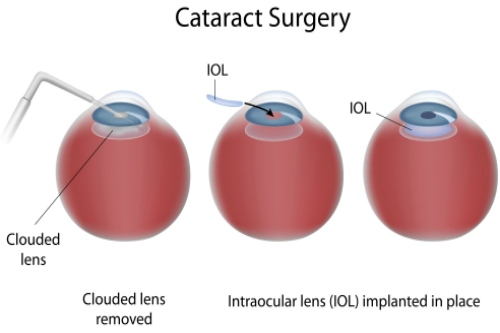

白内障专科:准屈光性手术

邵杰医师在白内障超声乳化联合功能性人工晶体植入方面经验充足,能够根据患者用眼需求定制散光矫正型、三焦点等个性化晶体,术后脱镜率高达92%。李凌副高医师则擅长糖尿病视网膜病变合并复杂白内障的联合手术,术后视力达标率优异。

特色技术:医院开展的微切口超声乳化手术,切口仅1.8mm,术后改善比较快,第二天即可获得良好视力。